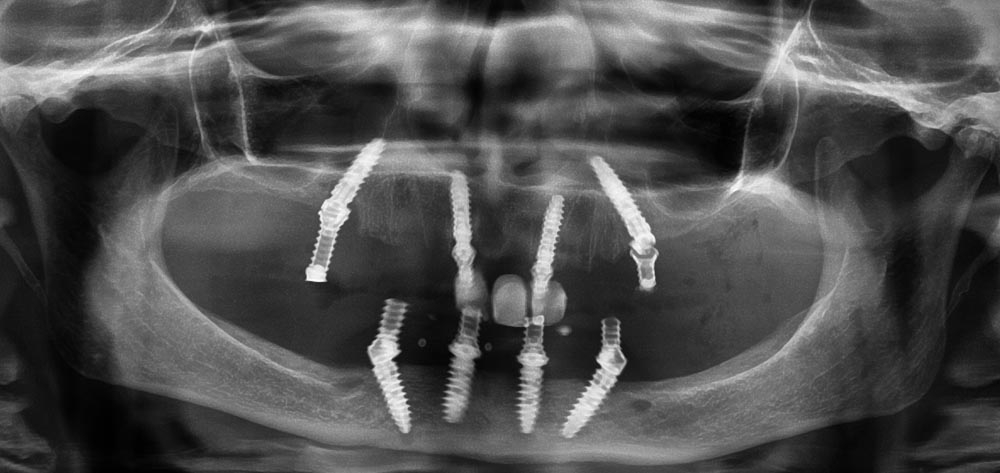

All on 4/ Teeth in a Day

Treatment Photos